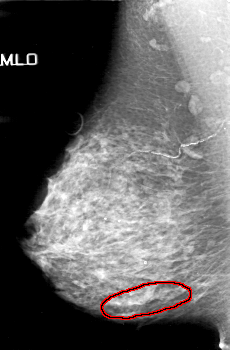

FILE: D_4154_1.RIGHT_MLO.OVERLAY

TOTAL_ABNORMALITIES 1

ABNORMALITY 1

LESION_TYPE CALCIFICATION TYPE AMORPHOUS DISTRIBUTION SEGMENTAL

ASSESSMENT 5

SUBTLETY 3

PATHOLOGY MALIGNANT

TOTAL_OUTLINES 1

BOUNDARY